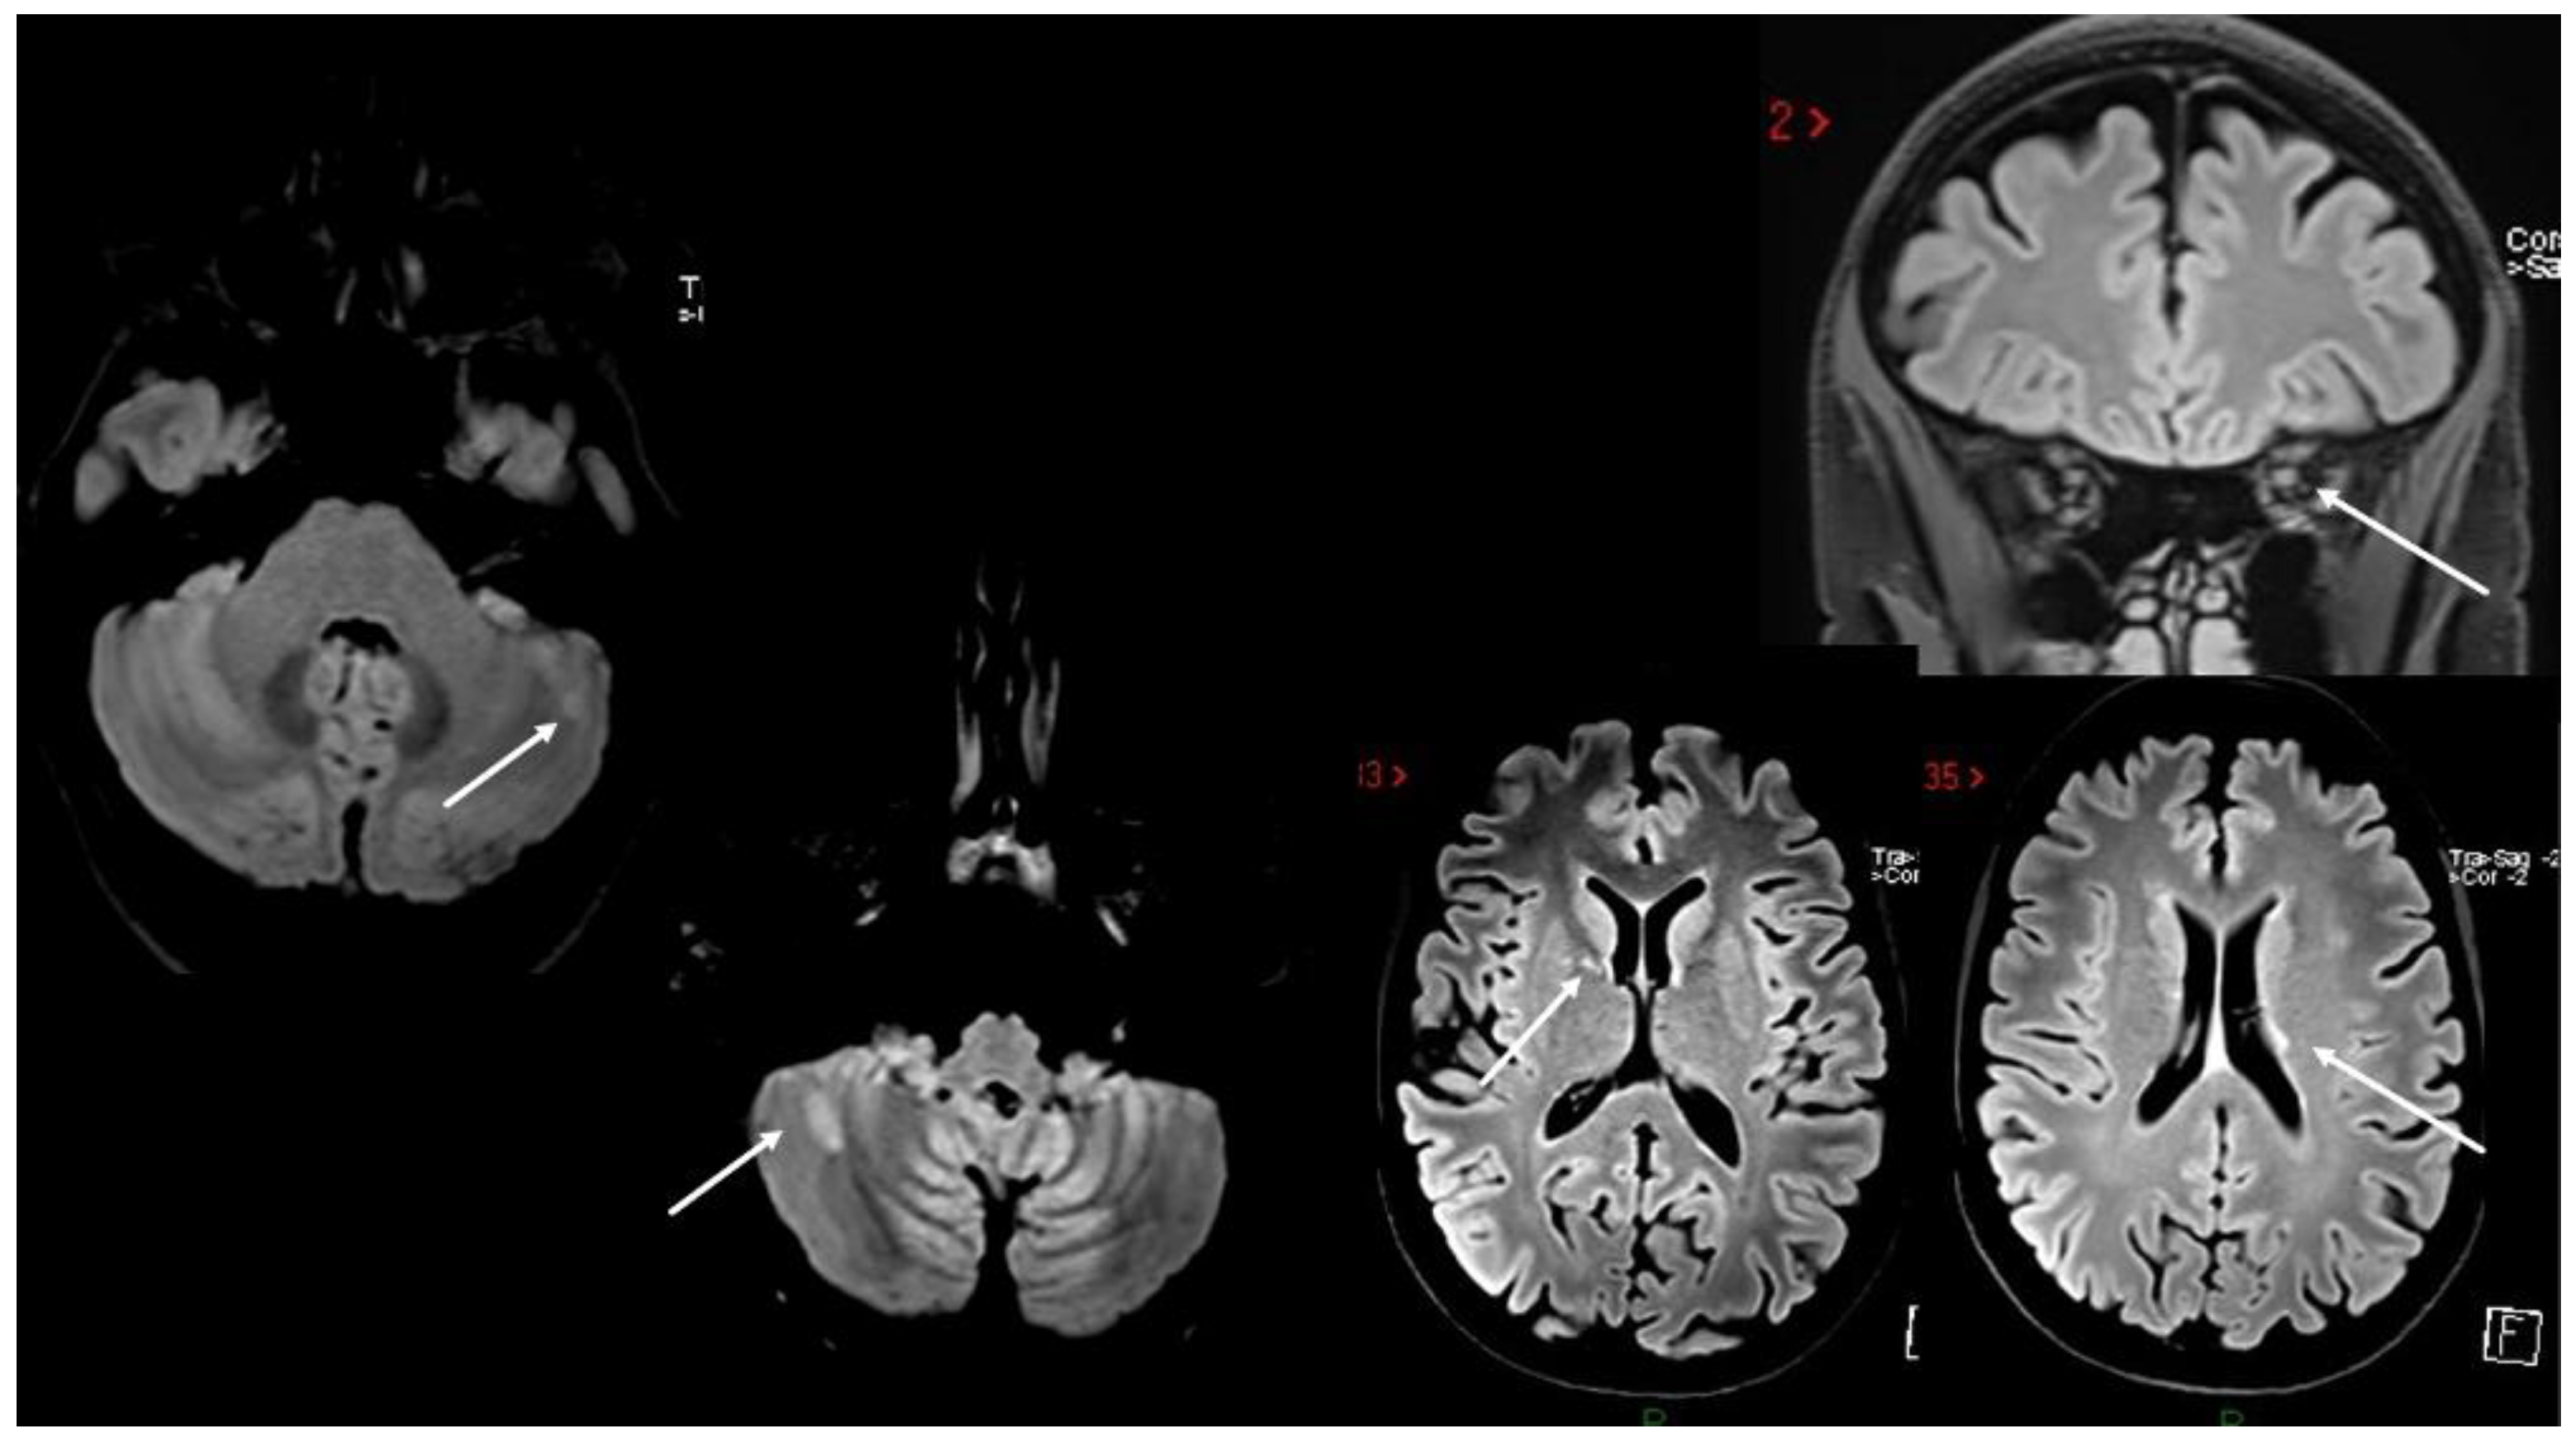

4. MS Onset after Vaccine Exposure

| Case 6 | BNT/2nd | 2 weeks | Multisymptomatic (gait/trunk ataxia, sphincter) | (MRI not in acute phase) | + | + | -/- | |

| Case 7 | ChAdOx1/1st | 1 week | SC | + | - | + | -/- | |

| Case 11 | BNT/1st | 1 week | SC | SC | + | + | NA | |

| Case 12 | BNT/1st | 2 weeks | SC | SC | + | + | +/+ | |

| Mele et al. [66] | Mod/1st | 2 days | Cerebellum | ST | + | + | −/+ | |

| Gernert et al. [63] 5 cases | BNT (4, 3 cases 1st, 1 case 2nd), 1 ChadoOx/2nd | 1–2 weeks | ON (2) BS (1) SC (1) BS+SC (1) | SC (2) BS/cerebellum (3) | + | +/+ | ||

| $ Watad et al. [69] 4 cases | BNT/1st (2) Mod/2nd (2) | 1 day–1 month | ST (1); cerebellum, SC (1) SC (2) | + | + | + | +/+ | |

| $ Nistri et al. [67] 2 cases | ChadOx/1st | 1 week | ON (2) IT (1) | + supratentorial | + | + | -/- | |